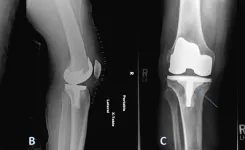

Dr. Timothy Alton is a dual-fellowship trained orthopedic surgeon specializing in Dr. Timothy Alton is a dual-fellowship trained orthopedic surgeon dedicated to providing the highest level of orthopedic care to his patients. He specializes in minimally invasive, muscle sparing techniques for hip and knee replacement surgeries and uses innovative, state of the art technologies to optimize patient outcomes. Dr. Alton specializes in robotic knee replacements and anterior approach total hip replacements. He uses a muscle sparing sub-vastus approach for robotic total knee replacements and minimally invasive anterior total hip replacements leveraging advanced navigation technology to improve patient outcomes and experiences.

Robotically Assisted Surgery

Minimally Invasive, Muscle Sparing Joint Replacement